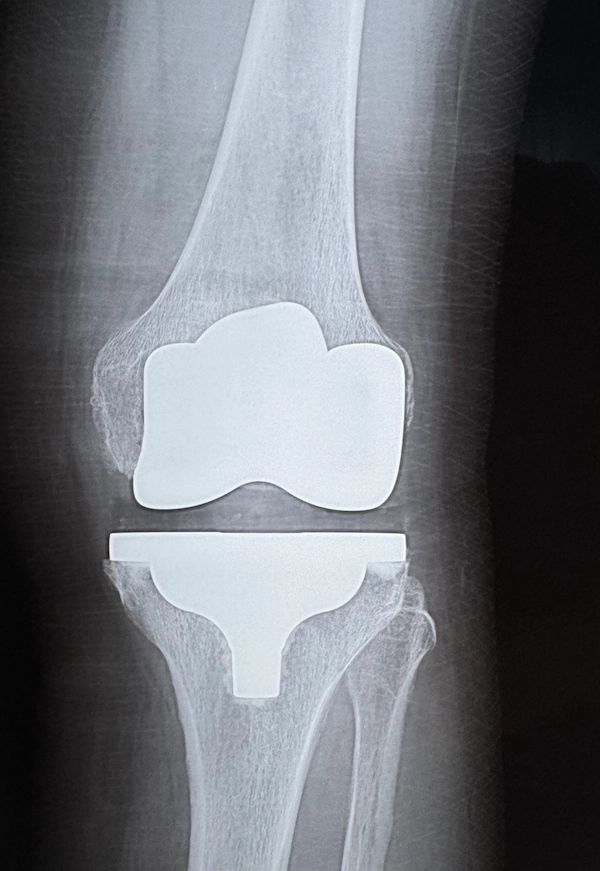

Заміна суглобів — радикальний метод лікування. Тому обов’язковим етапом перед операцією є комплексне обстеження: рентген суглобів, комп’ютерна томографія чи МРТ. За допомогою цих досліджень можна оцінити ступінь пошкодження суглобів і обрати оптимальні методи лікування.

Щоб правильно попередньо підібрати не тільки матеріал, а й форму та розмір протеза, лікар використовує результати обстежень — рентген та знімки комп'ютерної томографії, остаточно ж обирає параметри — безпосередньо під час операції.

Саме ретельна діагностика дає уявлення, як буде виглядати суглоб з ендопротезом у майбутньому та наскільки складною буде операція.